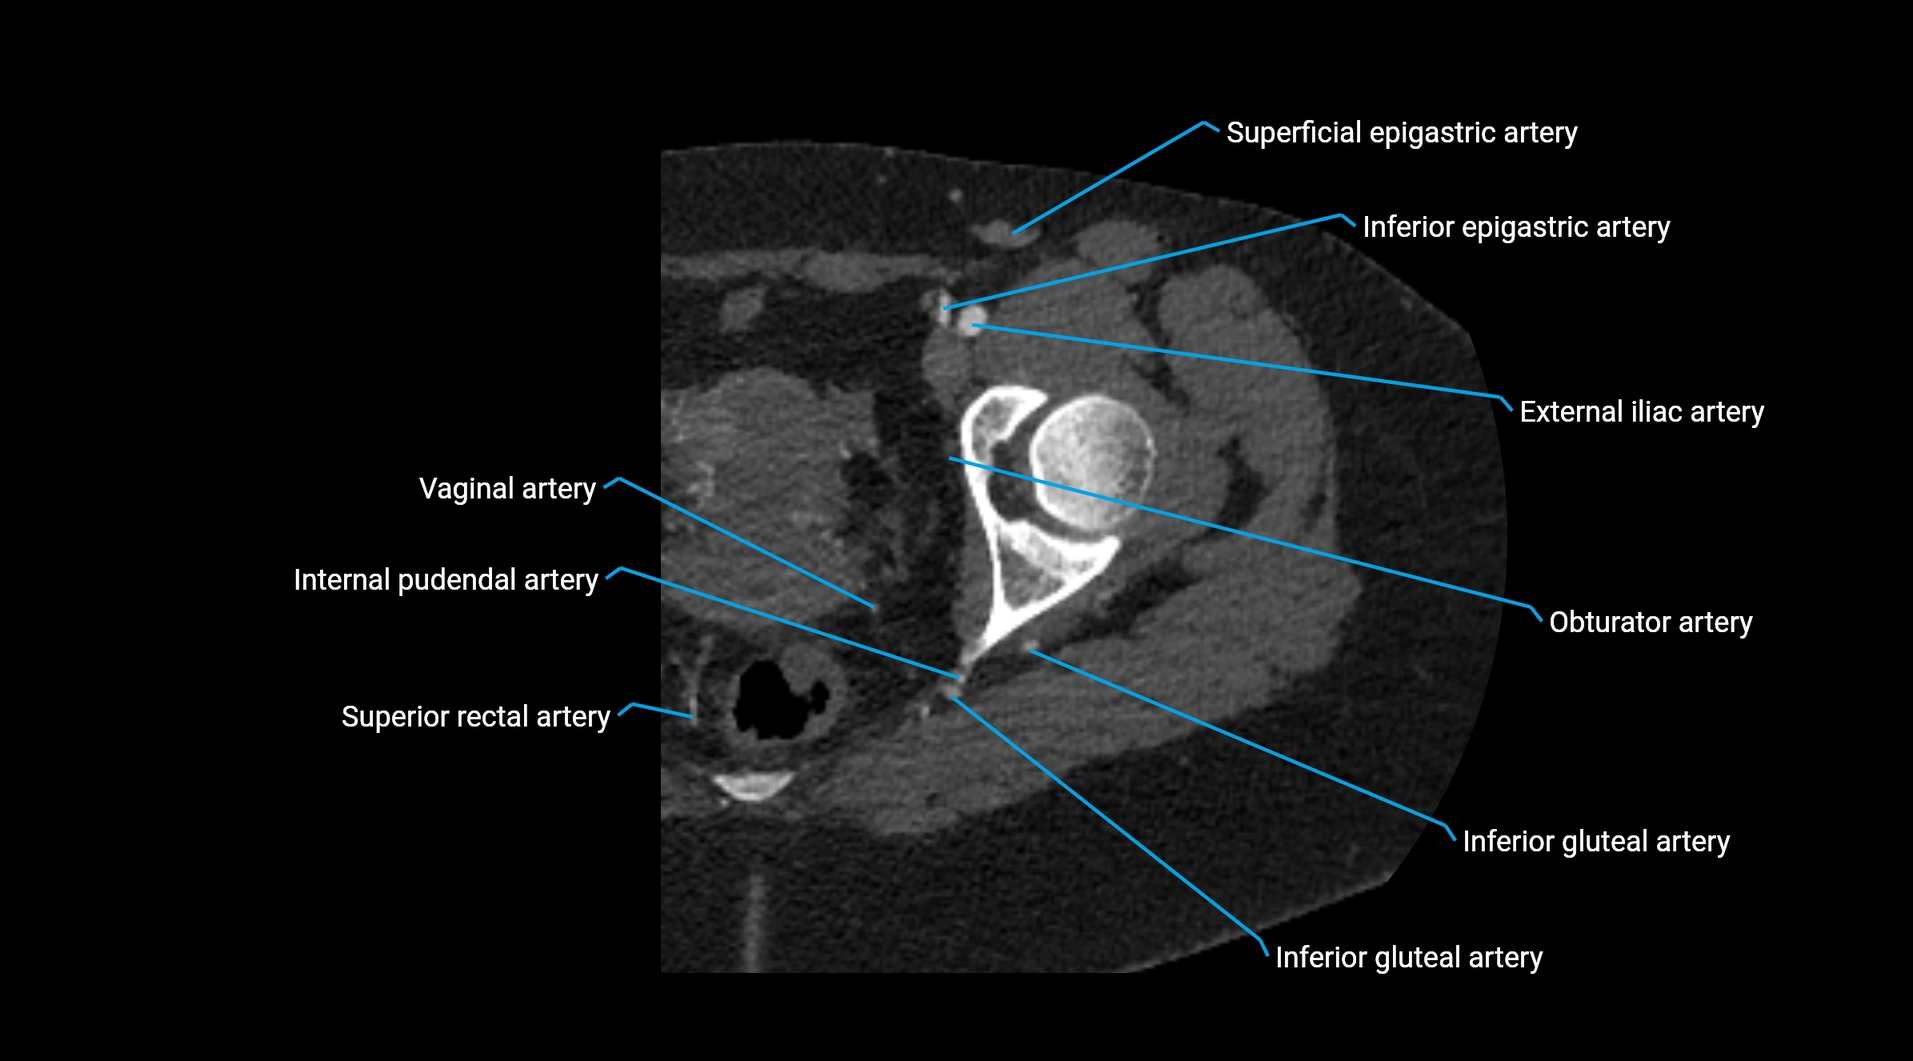

Contrast-enhanced CT (CTA):

• Gold standard for abdominal aortic imaging

• Provides excellent detail of lumen, wall, aneurysm, thrombus, and branch vessels

• Multiplanar and 3D reconstructions help in aneurysm measurement, stent graft planning, and dissection evaluation

• Detects acute rupture, traumatic injury, or occlusion with high sensitivity